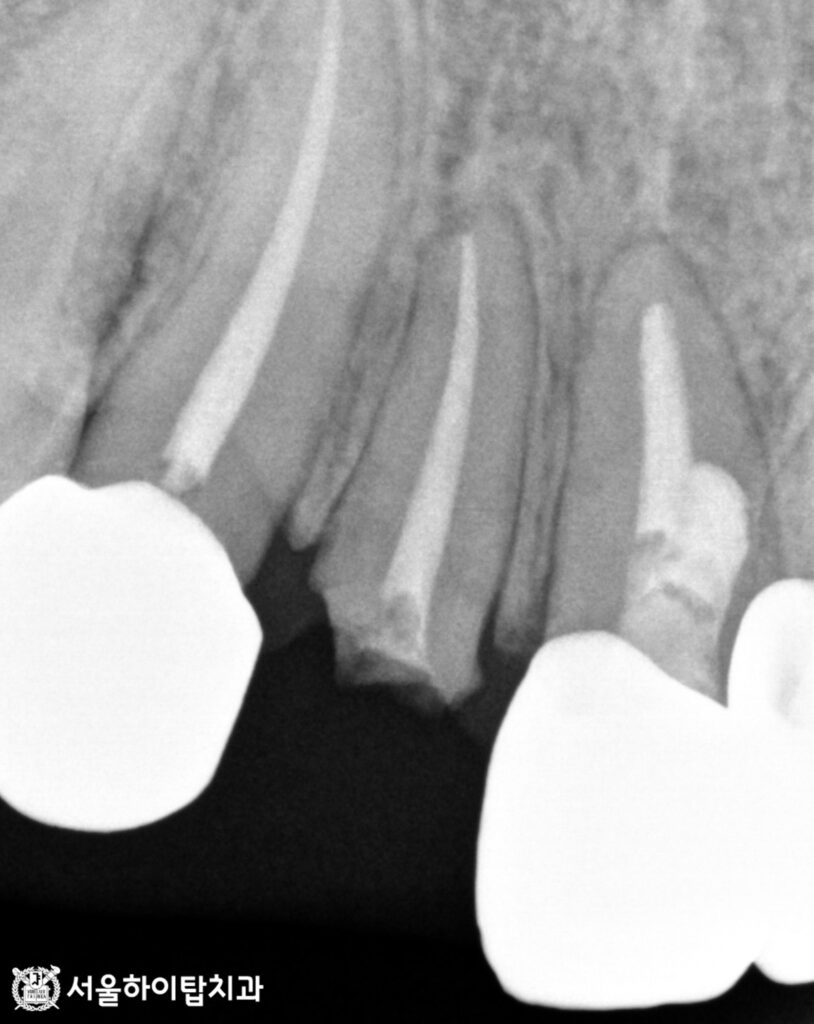

초진 구강 내 모습과 PA(치근단 방사선)사진을 살펴보겠습니다.

치관(치아 머리)이 통째로 파절된 모습을 볼 수 있습니다.

PA 사진에서 근관 내부가 전용 충전재인 가타퍼차로 채워져 있는 것을 확인할 수 있는데,

이를 통해 과거 신경치료를 받은 치아임을 알 수 있습니다.

즉, 신경치료 후 치아를 보호하기 위해 씌워졌던 크라운이 있었으나,

이번 파절로 인해 치관이 치근에서 완전히 분리된 상태임을 알 수 있습니다.